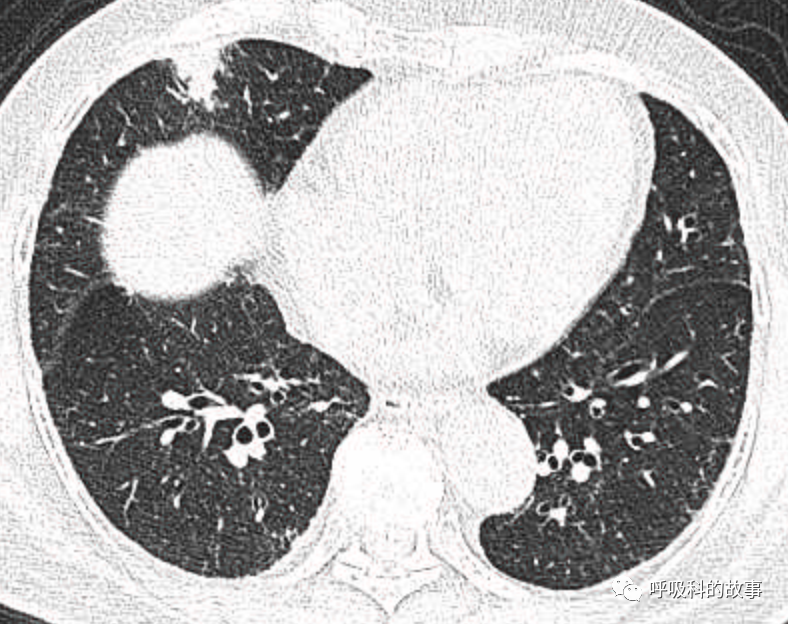

1个月前,我们收治了一个80多岁的男性患者,两肺多发结节和肿块,锁骨上淋巴结也触及肿大,在接诊时我们就预感不妙,患者很可能是患上了肺癌。后来经过穿刺后明确为大细胞神经内分泌癌,CT如下。

图1-11:该患者各个角度的影像图像

(上下滑动查看全部图片)

可是就在今年初,患者曾住在某院某科室,因为其他内科疾病住院。当时肺部CT也发现了在右中叶内侧段的高密度实变影,由于影像很类似肺炎,因此当成肺炎治疗。

图12-14:该患者各个角度的影像图像